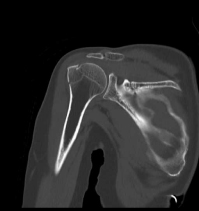

CT検査

整形外科領域

- 四肢

- 骨折・脱臼などの外傷